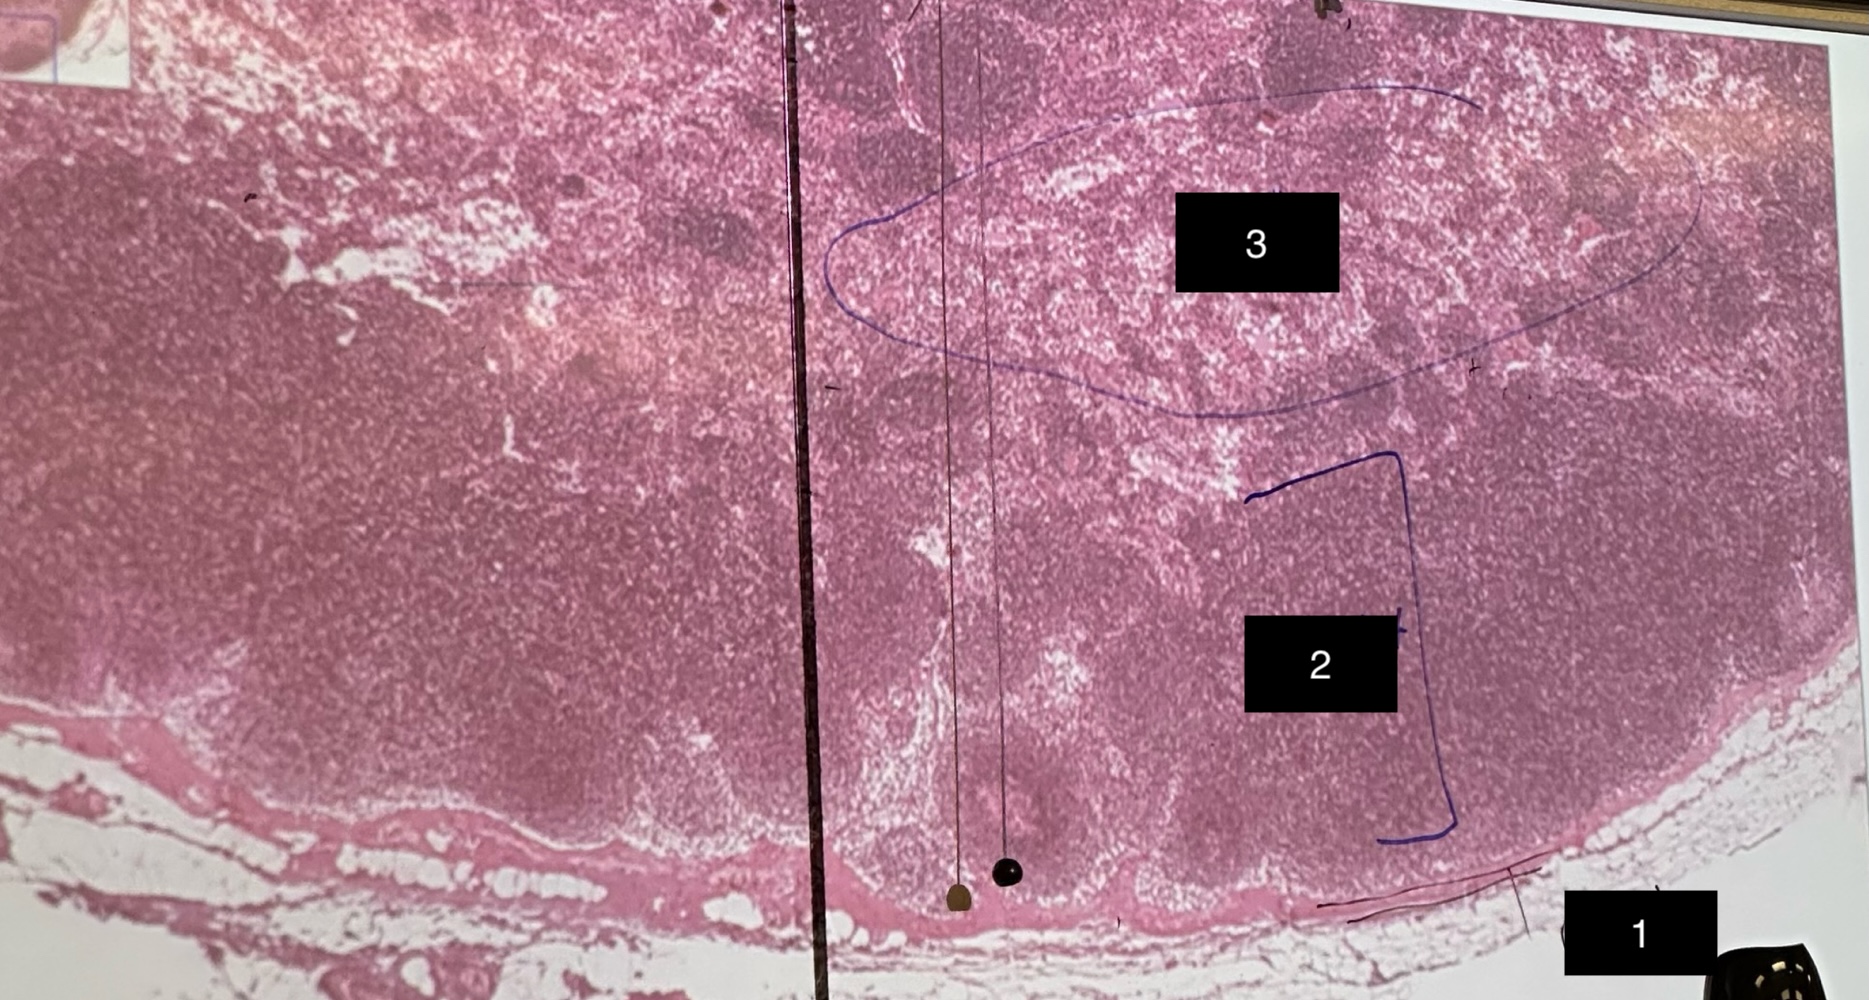

spleen

slide

capsule

1

red pulp

2

white pulp

3